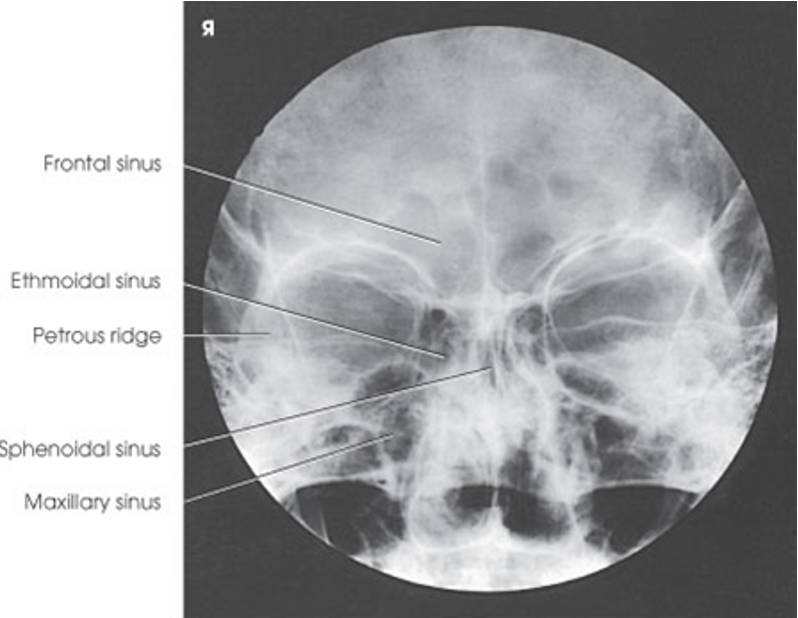

PA Axial of the Frontal and Ethmoidal Sinuses - Caldwell Method

Submentovertical of Ethmoidal & Sphenoidal Sinuses

Parietoacanthial of the Maxillary and sphenoidal sinuses - open-mouth waters method

Parietoacanthial projection of the maxillary sinuses - Waters Method

PA axial of the frontal and ethmoidal sinuses (Caldwell Method)

Parietoacanthial of the maxillary sinuses (Waters Method)

Parietoacanthial of the maxillary and sphenoidal sinuses (Open-mouth waters method)

Submentovertical of the ethmoidal and sphenoidal sinuses